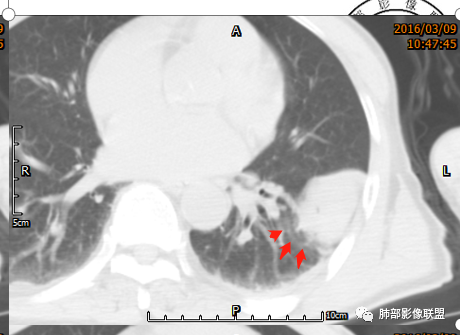

1)形态、大小:一般为单发,较小者呈类圆形或椭圆形,较大者呈浅分叶或不规则状;大小差异较大,直径1-25cm(有2个高峰期,大多数肿瘤直径<5cm,或者>10cm),肿瘤的大小与发生部位、病程长短有关;

2)生长方式:“铸型”生长;

定位:肿块长轴与胸膜平行,宽基底与胸膜相连,两端可见胸膜尾征,附近血管、支气管被推移,提示肺外胸膜起源;

定性:边缘光滑,浅分叶,边缘膨隆,提示肿瘤可能大,非炎性病变;

肿块动脉期明显不均匀强化,渐进性强化,呈“快进慢出”,其内可见小片、星芒状低密度区,提示胶原纤维或粘液变性区,首选胸膜来源孤立性纤维瘤,本例未见明显蛇纹血管征。